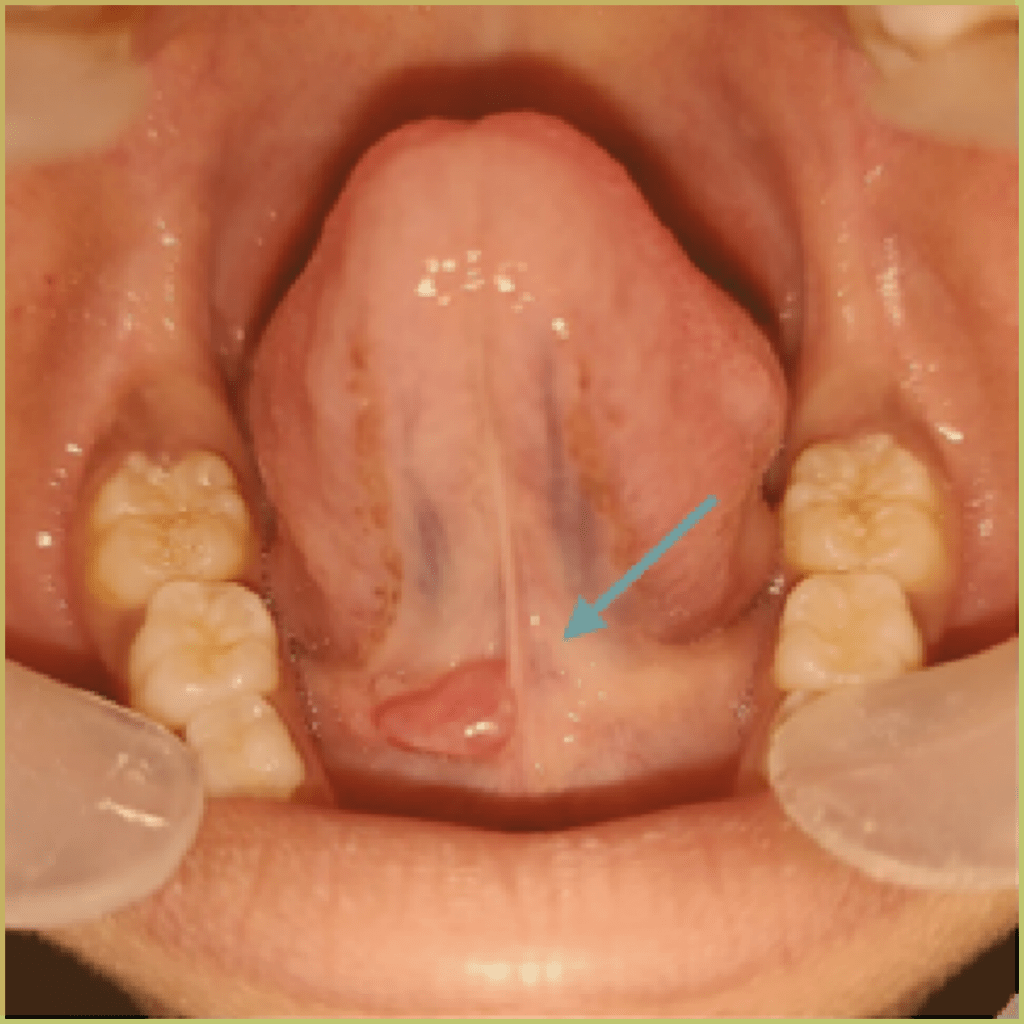

RANULAS

Ranulas are mucoceles that originate from major salivary glands, caused by the obstruction of the sublingual or submandibular gland ducts and subsequent extravasation of saliva into the soft tissues. When saliva accumulates above the mylohyoid muscles it is termed an oral ranula. When below the mylohyoid muscle in the fascial planes of the neck it is called a cervical or plunging ranula. The common clinical presentation includes:

- Unilateral, fluctuant swelling on the floor of the mouth.

- Usually has a bluish hue with slight translucent quality.

- Blockage is often caused by a salivary stone (sialolith).